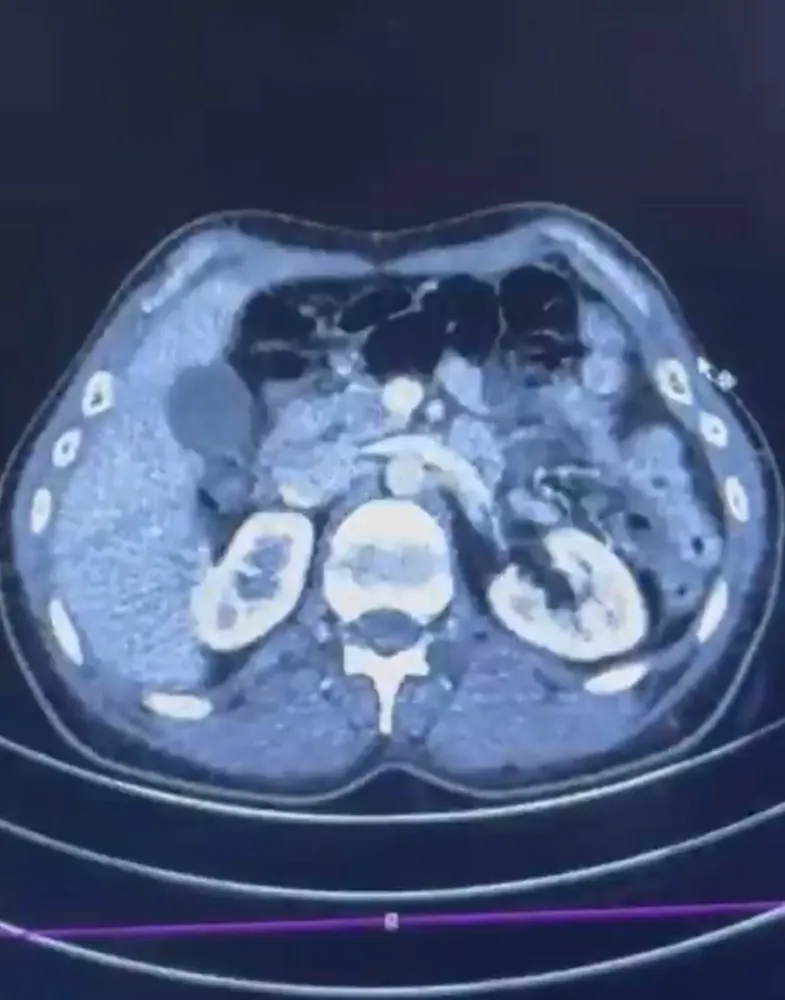

Edinilen bilgiye göre Narkotik Suçlarla Mücadele Şube Müdürlüğü ekiplerince uluslararası uyuşturucu madde ticareti yapan kurye şahıslara yönelik gerçekleştirilen çalışmalarda, İran’dan Türkiye'ye uyuşturucu madde getirdiği tespit edilen şüpheli şahısların yakalanması amacıyla operasyon düzenlendi. Düzenlenen operasyonda; S.C., R.B.C. ve G.M. yakalandı. S.C. ve R.B.C.'nin Kayseri Şehir Hastanesi'nde yapılan iç beden muayenelerinde, mide kısımlarında bulunduğu tespit edilen 50 adet kapsül şeklinde toplam 554 gram uyuşturucu madde ele geçirildi. Şüpheliler gözaltına alınarak haklarında 'Uyuşturucu Madde Ticareti Yapmak' işlem başlatıldı.